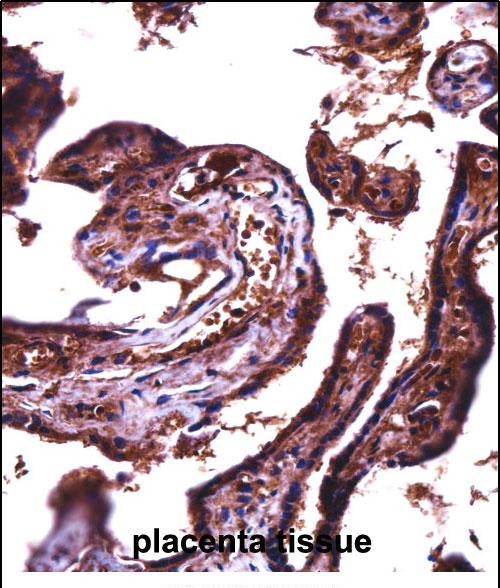

| IHC | 1/100-1/500 | Human,Mouse,Rat |

The JAM2 (N-term) antibody targets the N-terminal region of Junctional Adhesion Molecule 2 (JAM2), a member of the immunoglobulin superfamily involved in cell-cell adhesion and immune regulation. JAM2. also known as JAM-B or VE-JAM, is a transmembrane protein expressed on endothelial and immune cells, including lymphocytes and dendritic cells. It plays critical roles in maintaining vascular and epithelial barrier integrity, leukocyte migration, and immune synapse formation. The N-terminal extracellular domain of JAM2 mediates homophilic interactions with itself or heterophilic binding to JAM3 (JAM-C), facilitating cell adhesion and signaling.

This antibody is commonly used in research to study JAM2 localization, expression levels, and function in physiological and pathological contexts, such as inflammation, angiogenesis, and cancer metastasis. It is validated for applications like Western blotting, immunohistochemistry, and flow cytometry. Studies using JAM2 (N-term) antibodies have highlighted its involvement in autoimmune diseases, tumor microenvironment modulation, and lymphocyte trafficking. By detecting the N-terminal epitope, the antibody helps elucidate mechanisms underlying endothelial barrier disruption or immune cell recruitment in diseases like multiple sclerosis or atherosclerosis. Its specificity makes it a valuable tool for exploring JAM2's role in intercellular communication and therapeutic targeting.